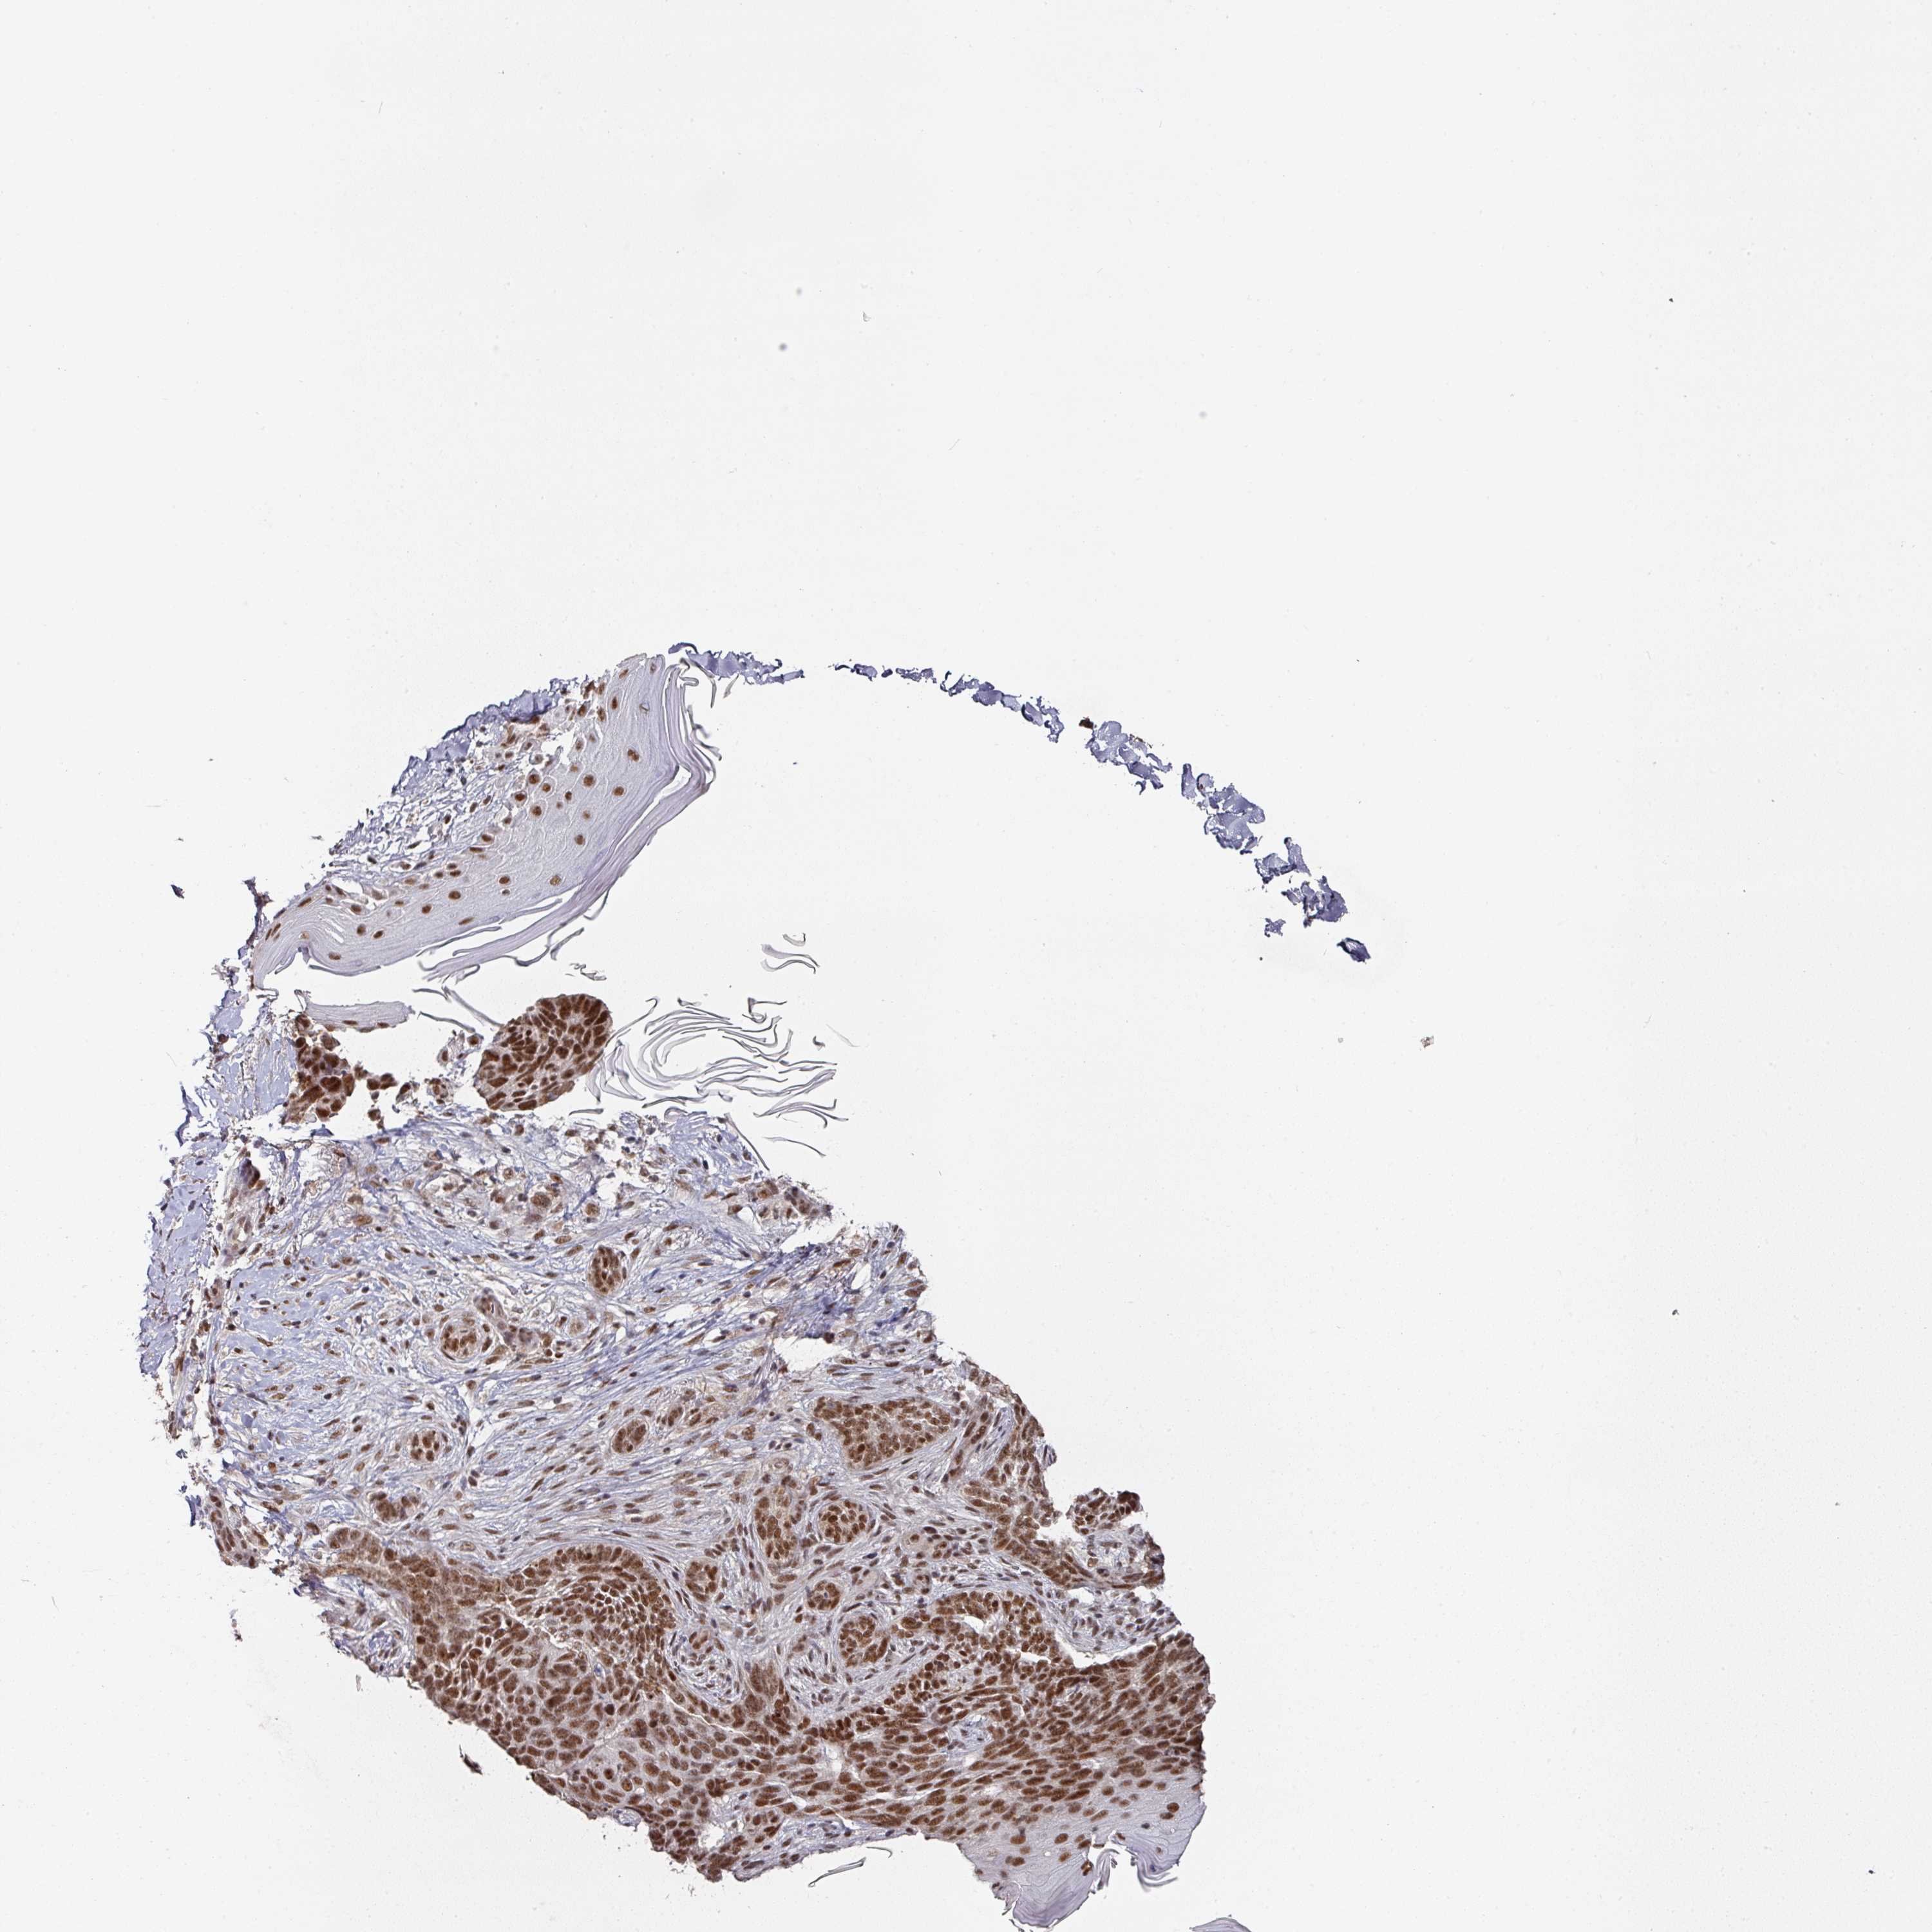

SKIN CANCER - Protein expressioni

A mouse-over function shows sample information and annotation data. Click on an image to view it in a full screen mode. Samples can be filtered based on level of antibody staining by selecting one or several of the following categories: high, medium, low and not detected. The assay and annotation is described here.

Antibody stainingi

Antibody staining in the annotated cell types in the current human tissue is reported as not detected, low, medium, or high, based on conventional immunohistochemistry profiling in selected tissues. This score is based on the combination of the staining intensity and fraction of stained cells.

Each image is clickable and will lead to virtual microscopy that enables deeper exploration of all samples and also displays staining intensity scores, fraction scores and subcellular localization as well as patient and tissue information for each sample.

Antibody HPA051587

Antibody CAB026384

Staining

High

Medium

Low

Not detected

Intensity

Strong

Moderate

Weak

Negative

Quantity

>75%

75%-25%

<25%

None

Location

Nuclear

Cytoplasmic/membranous

Cytoplasmic/membranous,nuclear

Basal cell carcinoma